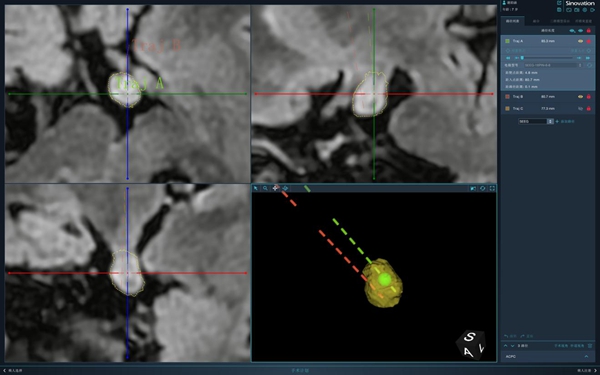

插入腫瘤的2根電極示意圖。重醫(yī)附屬兒童醫(yī)院供圖

經(jīng)過充足的術(shù)前準(zhǔn)備后,翟瑄帶領(lǐng)團(tuán)隊利用手術(shù)機器人精準(zhǔn)確定腫瘤位置,在機器人引導(dǎo)下,準(zhǔn)確地將兩根立體定向深部電極同時置入到女童顱內(nèi)腫瘤里,再通過視頻腦電圖監(jiān)測確定腫瘤內(nèi)部具體“異常放電”的電極點及強度,利用反向電流加熱電極對腫瘤進(jìn)行熱凝損毀,最終“摧毀”腫瘤。這樣就能達(dá)到消除癲癇發(fā)作的作用,待手術(shù)成功后再將電極安全取出。